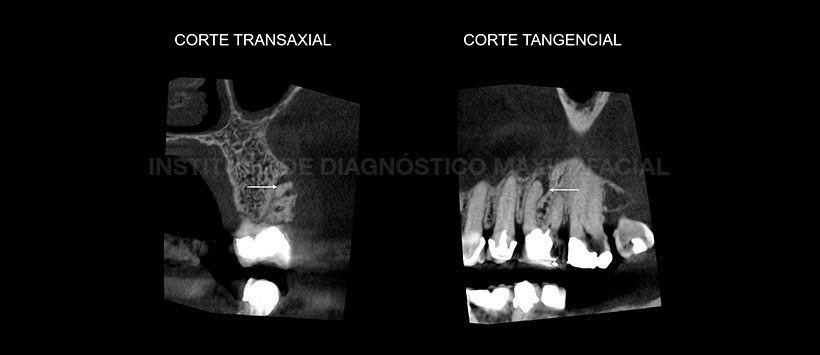

A la evaluación de la tomografía volumétrica de haz cónico (Figura 2 y Figura 3), se evidencio que la pieza 26 presenta un cuarto conducto sin obturar (mesiopalatino), motivo por el cual cuando se evaluó en una segunda vista transaxial y tangencial (Figura 4), encontramos que dicho conducto conllevaba a la formación de proceso osteolítico apical.